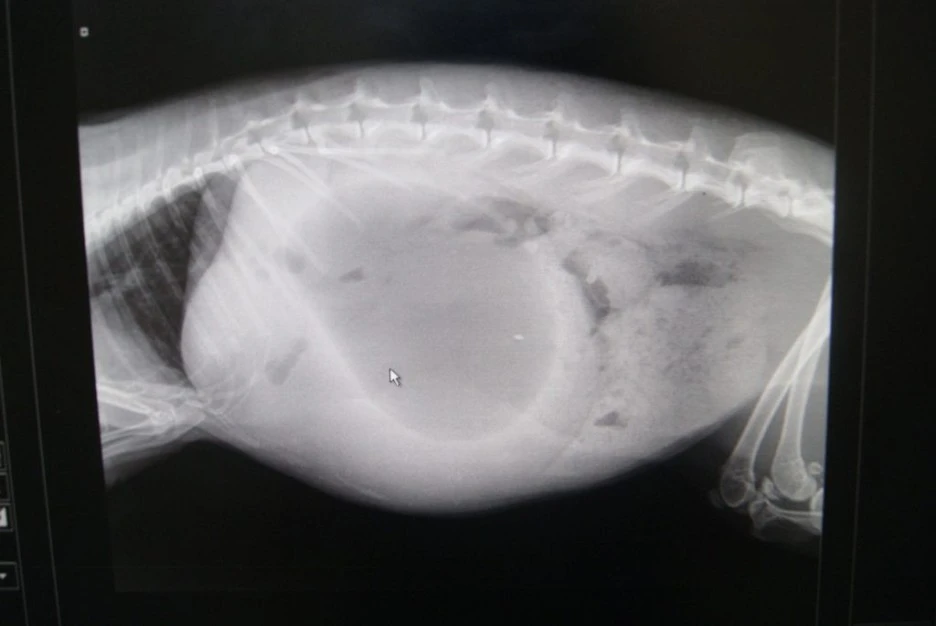

문제는 토끼가 이처럼 탄수화물이 많은 음식을 지속적으로 섭취할 경우 비만이 되기 쉽고 소화 불량과 장 정체를 일으킬 수 있습니다. 또한 탄수화물을 소화하면서 나온 가스가 위에 가득 차면서 생기는 고창증(Bloating)도 생길 수 있습니다. 토끼는 건초가 반드시 주식이며 섬유질이 많아야 하고 사료마저도 조심해서 줘야 할 정도죠. 심지어 토끼는 질긴 건초로 이갈이를 해야 하는데 너무 부드러운 음식만 먹으면 치아가 갈리지 않아 자칫 수술을 해야 할 수도 있죠.

우사기는 반드시 비만과 고창증을 조 심해야 하며 지금이라도 건초 위주의 섬유질이 풍부한 풀 위주로 식단을 바꾸는 것이 좋습니다. 문제는 이러한 자극적인 음식에 이미 적응되어 버렸을 것이고 편식도 있을 것으로 보이는데 이를 바꾸는 것은 쉽지 않을 것 같습니다.

Rabbit-SI-obstruction-3-1024x685.jpg?type=w1 출처 : Vetafarm